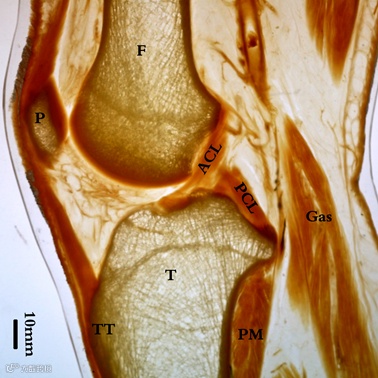

膝关节P45 断层塑化切片(矢状切)

P45 技术制备的标本可以大范围地在透明状态下对标本的细微结构进行观察,使其成为填补大体结构与组织学研究之间空白的方法学突破,在临床解剖学研究领域有极高的应用价值。